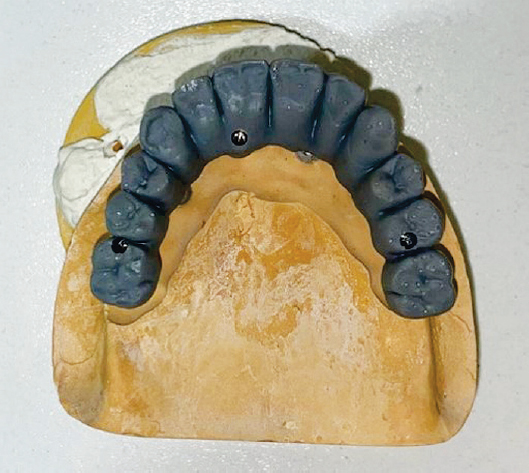

На рисунке 23 изображена постоянная конструкция, выполненная из диоксида циркония до соединения конструкции с титановой балкой. Затем готовая конструкция и балка соединяются цементом (рис. 24).

Рис. 23. Вид постоянной конструкции до цементировки с титановой балкой

Fig. 23. View of the permanent structure before cementation with a titanium beam

Рис. 24. Вид готовой постоянной конструкции

Fig. 24. View of the finished permanent structure